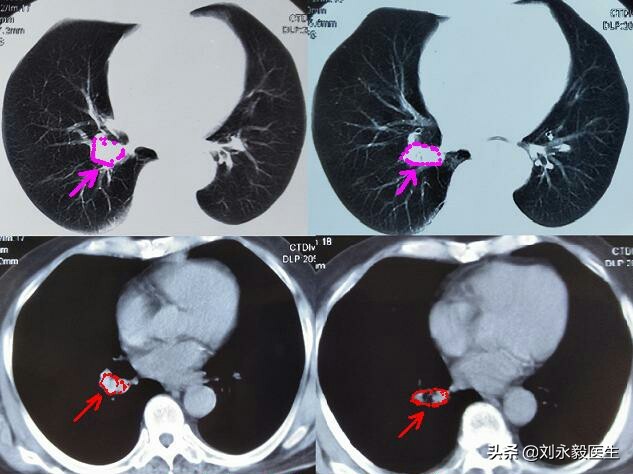

某女、肺腺癌,2009年、46歲時以咳嗽發現左肺下葉腺癌,胸水形成、無法手術。加入“吉非替尼”臨床研究,1年后耐藥,間斷化療多次,病情一直穩定。2016年底肺部腫瘤增大,基因檢測后,T790M存在突變,9291(非正版)治療兩年,生活自理,還做了一段時間的保潔員。近日說話聲音嘶啞,復查CT片左下肺腫瘤還很小、沒有胸水,縱膈淋巴結腫大……,這例肺腺癌病人發現時即是晚期,一直不斷治療,目前生存時間快10年了。

上圖是某患者初診肺癌時的胸部CT,腫瘤不大,如果此時手術,生存時間可能要好很多,很遺憾,采取了“中藥化療”,2018年11月胸悶氣短,檢查CT發現氣管隆突處腫瘤堵塞主支氣管,如下CT圖。